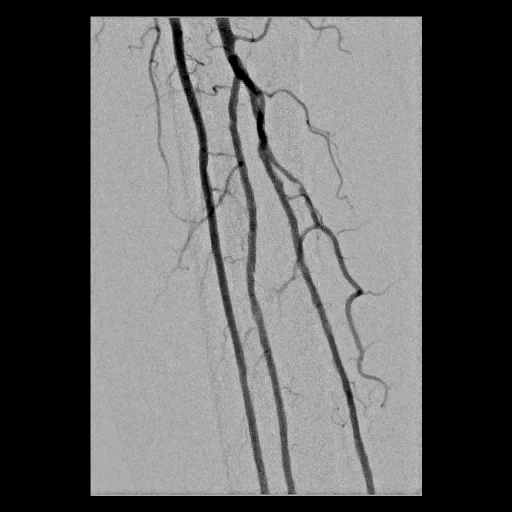

Figure 1. 淺股動脈的使用經皮腔內血管成形術治療

A. 右側淺股動脈慢性全閉塞

B. 氣球擴張術治療

C. 血管支架置放

D. 打通右側淺股動脈